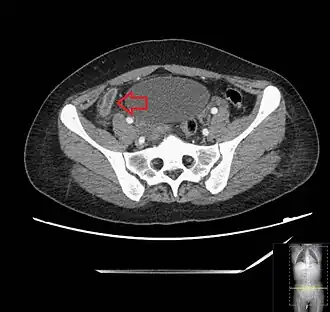

_(Radiopaedia_154713-127660_Axial_1).jpg)

Computed tomography

Where it is readily available, computed tomography (CT) has become frequently used, especially in people whose diagnosis is not obvious on history and physical examination. Although some concerns about interpretation are identified, a 2019 Cochrane review found that the sensitivity and specificity of CT for the diagnosis of acute appendicitis in adults was high.[63] Concerns about radiation tend to limit use of CT in pregnant women and in children, especially with the increasingly widespread usage of MRI.[64][65]

The accurate diagnosis of appendicitis is multi-tiered, with the size of the appendix having the strongest positive predictive value, while indirect features can either increase or decrease sensitivity and specificity. A size of over 6 mm is both 95% sensitive and specific for appendicitis.[66]

However, because the appendix can be filled with fecal material, causing intraluminal distention, this criterion has shown limited utility in more recent meta-analyses.[67] This is as opposed to ultrasound, in which the wall of the appendix can be more easily distinguished from intraluminal feces. In such scenarios, ancillary features such as increased wall enhancement as compared to adjacent bowel and inflammation of the surrounding fat, or fat stranding, can be supportive of the diagnosis. However, their absence does not preclude it. In severe cases with perforation, an adjacent phlegmon or abscess can be seen. Dense fluid layering in the pelvis can also result, related to either pus or enteric spillage. When patients are thin or younger, the relative absence of fat can make the appendix and surrounding fat stranding difficult to see.[67]